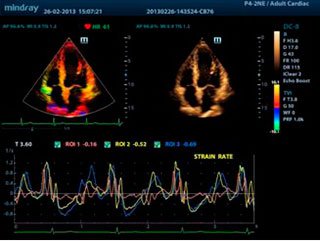

УЗИ сердца

Mindray DC-8 EXP обеспечивает высочайшую производительность для сердечно-сосудистой визуализации и анализа.